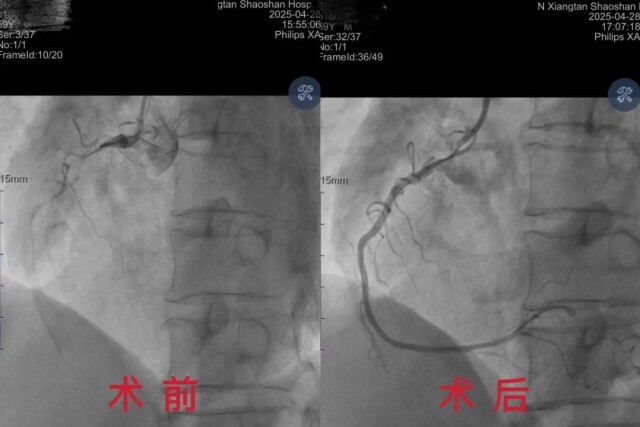

面对患者微弱的脉搏,赵帅迅速制定介入手术方案。凭借丰富的手感与经验,精准找到目标血管并成功置入导丝。然而,死神在此刻发难——患者心脏突发室颤,心电监护仪发出刺耳警报。“先除颤!稳定生命体征!”赵帅果断下达指令。团队默契配合,连续电除颤,同时持续进行心肺复苏。待患者心律稍有稳定,赵帅立即操作导管,穿过狭窄堵塞处,顺利送入球囊,精准地释放支架,原本闭塞的血管逐渐恢复通畅,让心脏重获新生。